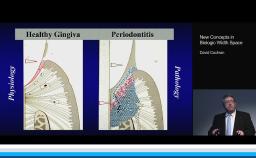

- describe soft and hard tissue alterations after tooth extraction

- describe treatments to compensate for soft and hard tissue changes